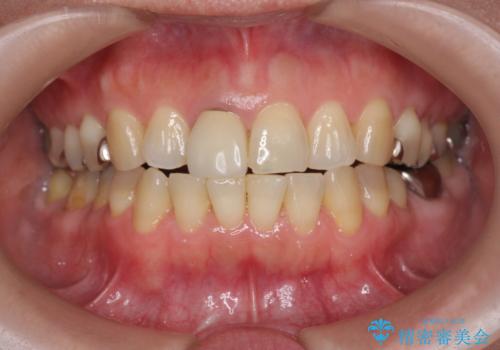

セラミッククラウン 歯ぐきの黒ずみの改善

- 十数年前に治療した前歯のクラウンの歯ぐきの位置が変化し、黒いラインが見え審美性の改善を求めて来院されました。

ファイバーコアのやりかえを行ったのち、金属を用いないジルコニアクラウンによる再補綴を行い前歯の審美性の向上を計画します。

近年前歯のクラウン製作に用いられるジルコニアクラウンは、金属を用いていないため経年的に歯ぐきの位置が変わっても黒いラインが見えることなく審美性の意地が期待できます。